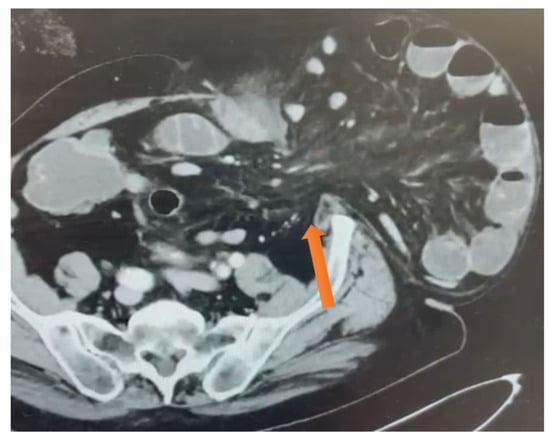

Figure 2.

Axial CT scan demonstrating intrasaccular septation (see the orange arrow) that explains the internal compartmentalization and strangulation within this chronic irreducible incisional hernia.